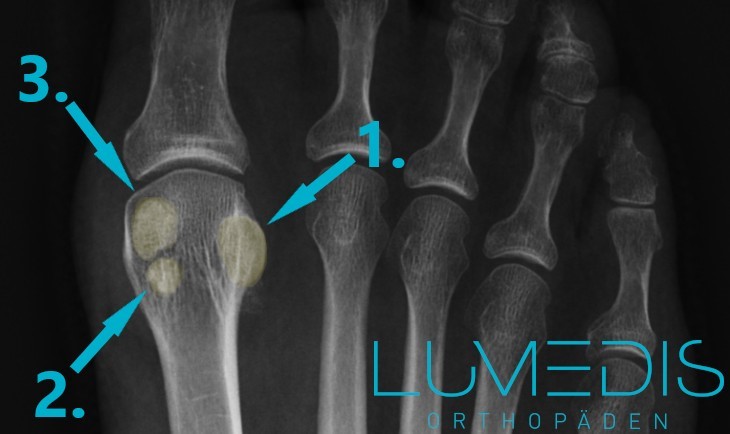

Die türkisen Pfeile zeigen auf eine Entzündung des medialen (inneren) und lateralen (äußeren) Sesambeins.

Röntgenbild eines geteilten Sesambeins